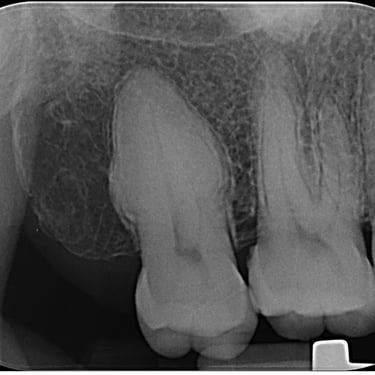

Hipercementosis

La hipercementosis es un engrosamiento anormal del cemento radicular del diente, a menudo debido a una inflamación crónica o trauma.

Los pacientes generalmente no tienen síntomas, pero la condición puede ser descubierta en una radiografía.

El tratamiento no suele ser necesario a menos que cause problemas con la extracción del diente.